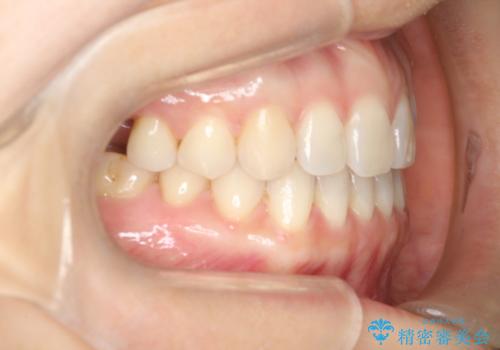

【インビザラインで再矯正】マウスピース矯正で隙間を閉じたい

- 過去に矯正を行ったあと、前歯の後戻りを主訴に来院されました。

マウスピース矯正にて隙間を閉じる計画をたて、治療を行いました。